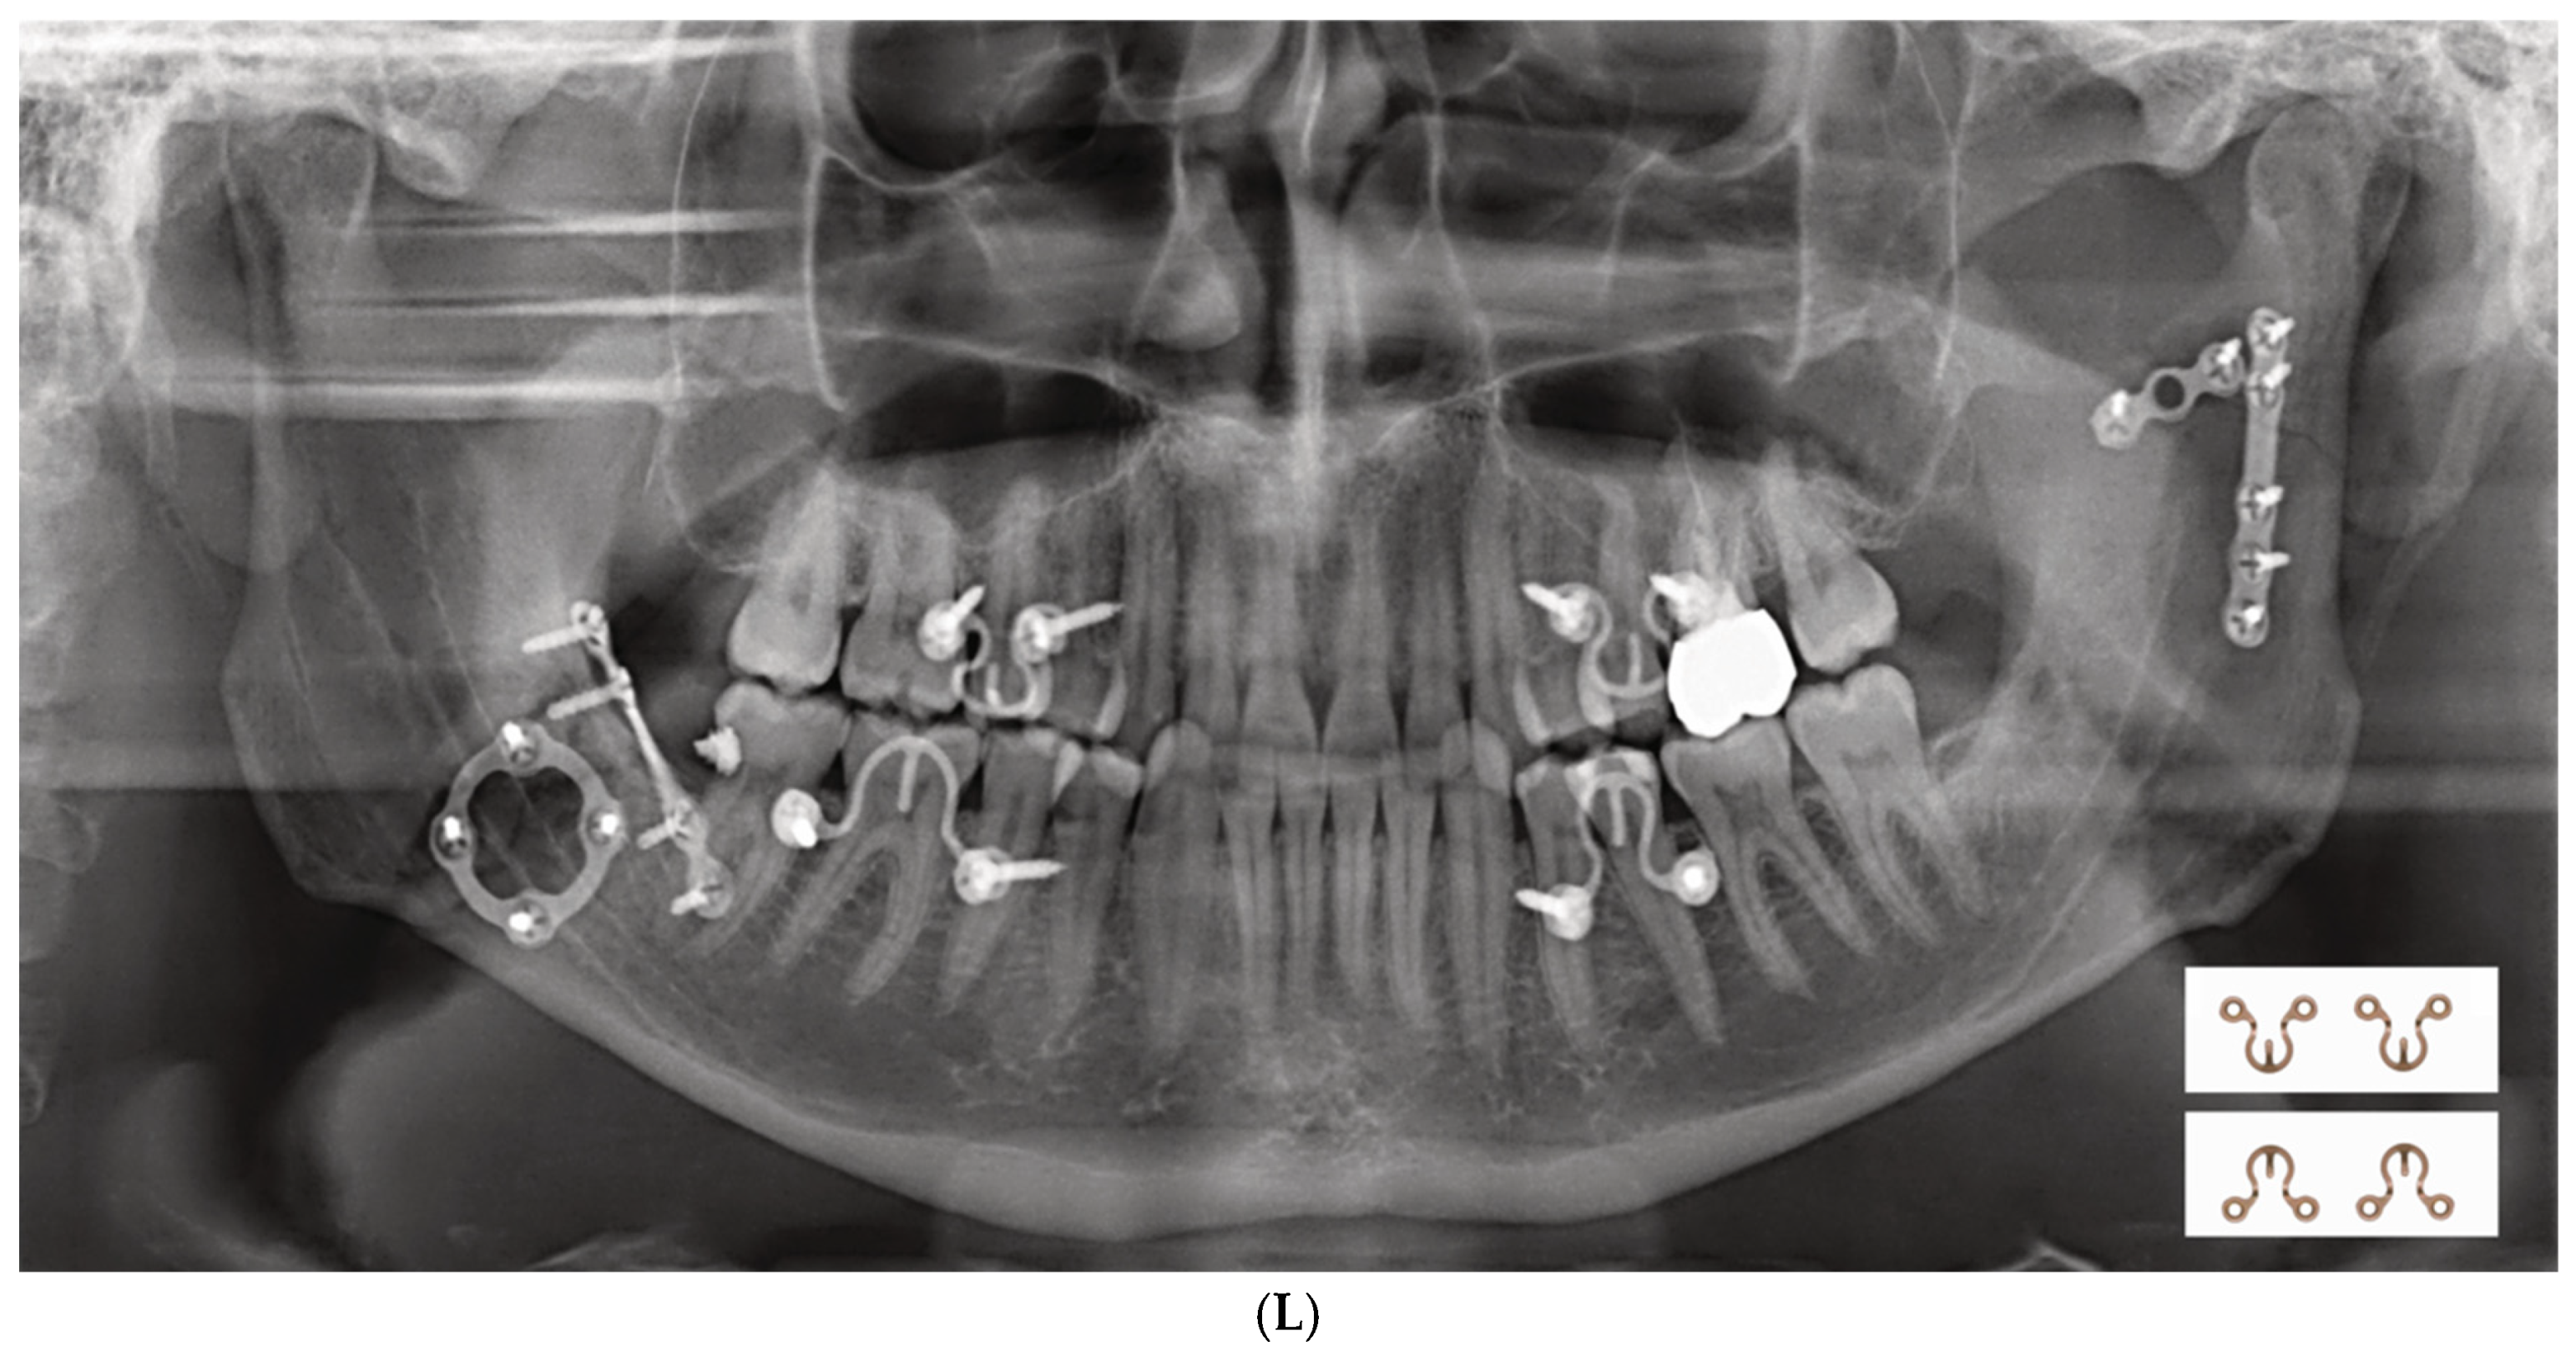

2.1. Locking Adaption Plate and MMF Nuts

4.1. Locking Adaptation Plate and MMF Nuts

4.2. Predecessor—First-Wave Plate Version

4.3. Second Wave Plate Version: Matrix WaveTM MMF System